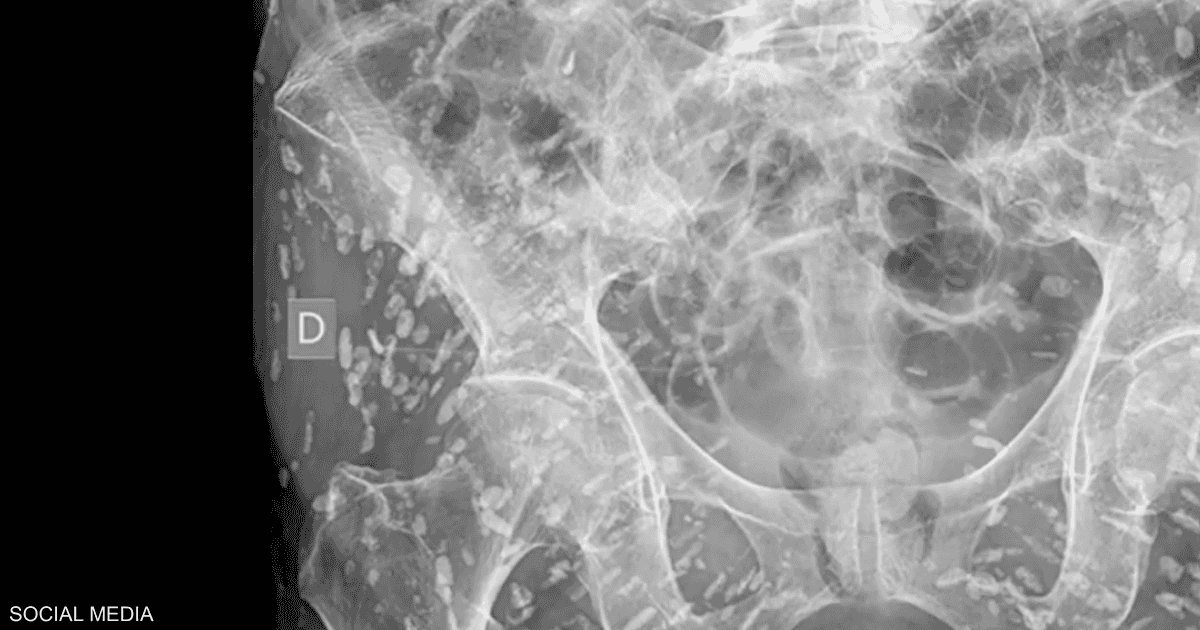

ووفق ما نشرت صحيفة ديلي ميل البريطانية فقد شارك الدكتور سام غالي طبيب الرعاية العاجلة في فلوريدا صورة الأشعة على وسائل التواصل الاجتماعي واعتبرها “واحدة من أكثر الأشعة السينية جنونا” التي رآها على الإطلاق.

وقال غالي عن الأكياس: “إنهم في كل مكان وهم لا حصر لهم، لا يمكنك حتى أن تبدأ في عدهم جميعا”.

وبين أن هذه الأكياس يمكنها الانتقال إلى أي مكن في الجسم مضيفا أنه: “في هذا المريض انتقلت بشكل كبير إلى الأنسجة الرخوة في الوركين والساقين.”